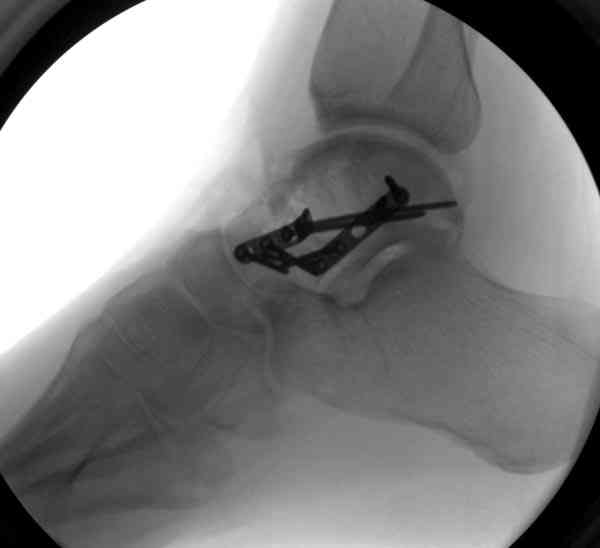

И второй случай из недавней ташкентской практики, (извините за качество ренгенограммы и только в одной проекции) случай падения с высоты (кстати моего друга - известного киноактера) - открытый

смещенный перелом тарана, с переломом переднего края дистального эпиметафиза большеберцовой кости.

При поступлении в приемной сделана первичная обработка с ушиванием открытой латеральной раны и вытяжением за пятку.

Из-за отсутствия времени пришлось оперировать на второе утро, из материала, что имеем на месте, фиксирован двумя шурупами, а третий-это контур сломанного жойстика в 4 мм. На дистальный медиальный конец тибиа antiglide 3.5 мм пластина. Через пару дней выписан и несмотря на предупреждение, самостоятельно начал нагрузку в 4 недели, время не ждет, снимается в боевике в Росийской Федерации.